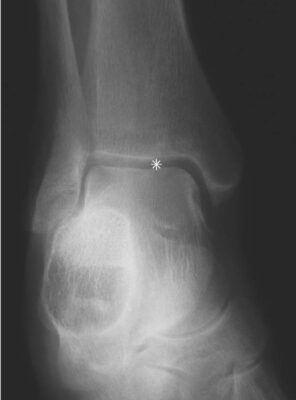

LIÊN HỆ X QUANG

Ghi chú chữ viết tắt:

- S =Spur; gai xương (gót)